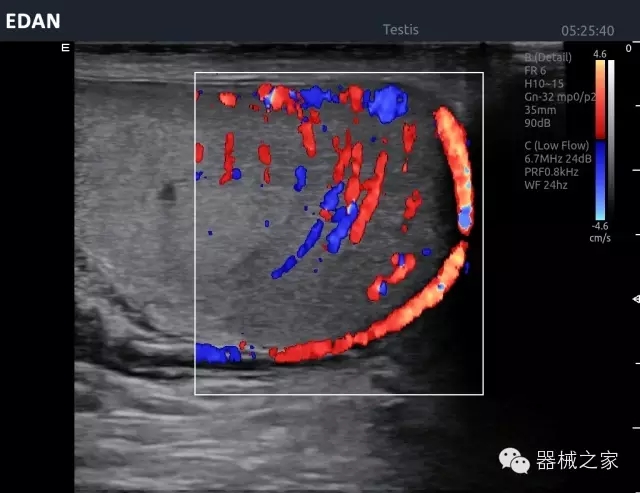

臨床圖片賞析

睪丸低速血流

臍帶血流

頸動(dòng)脈頻譜